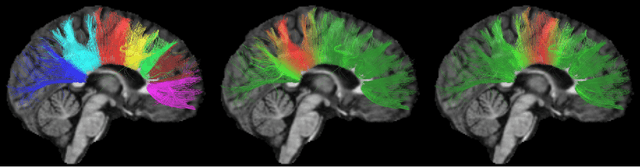

Diffusion magnetic resonance imaging, a non-invasive tool to infer white matter fiber connections, produces a large number of streamlines containing a wealth of information on structural connectivity. The size of these tractography outputs makes further analyses complex, creating a need for methods to group streamlines into meaningful bundles. In this work, we address this by proposing a set of kernel dictionary learning and sparsity priors based methods. Proposed frameworks include L-0 norm, group sparsity, as well as manifold regularization prior. The proposed methods allow streamlines to be assigned to more than one bundle, making it more robust to overlapping bundles and inter-subject variations. We evaluate the performance of our method on a labeled set and data from Human Connectome Project. Results highlight the ability of our method to group streamlines into plausible bundles and illustrate the impact of sparsity priors on the performance of the proposed methods.